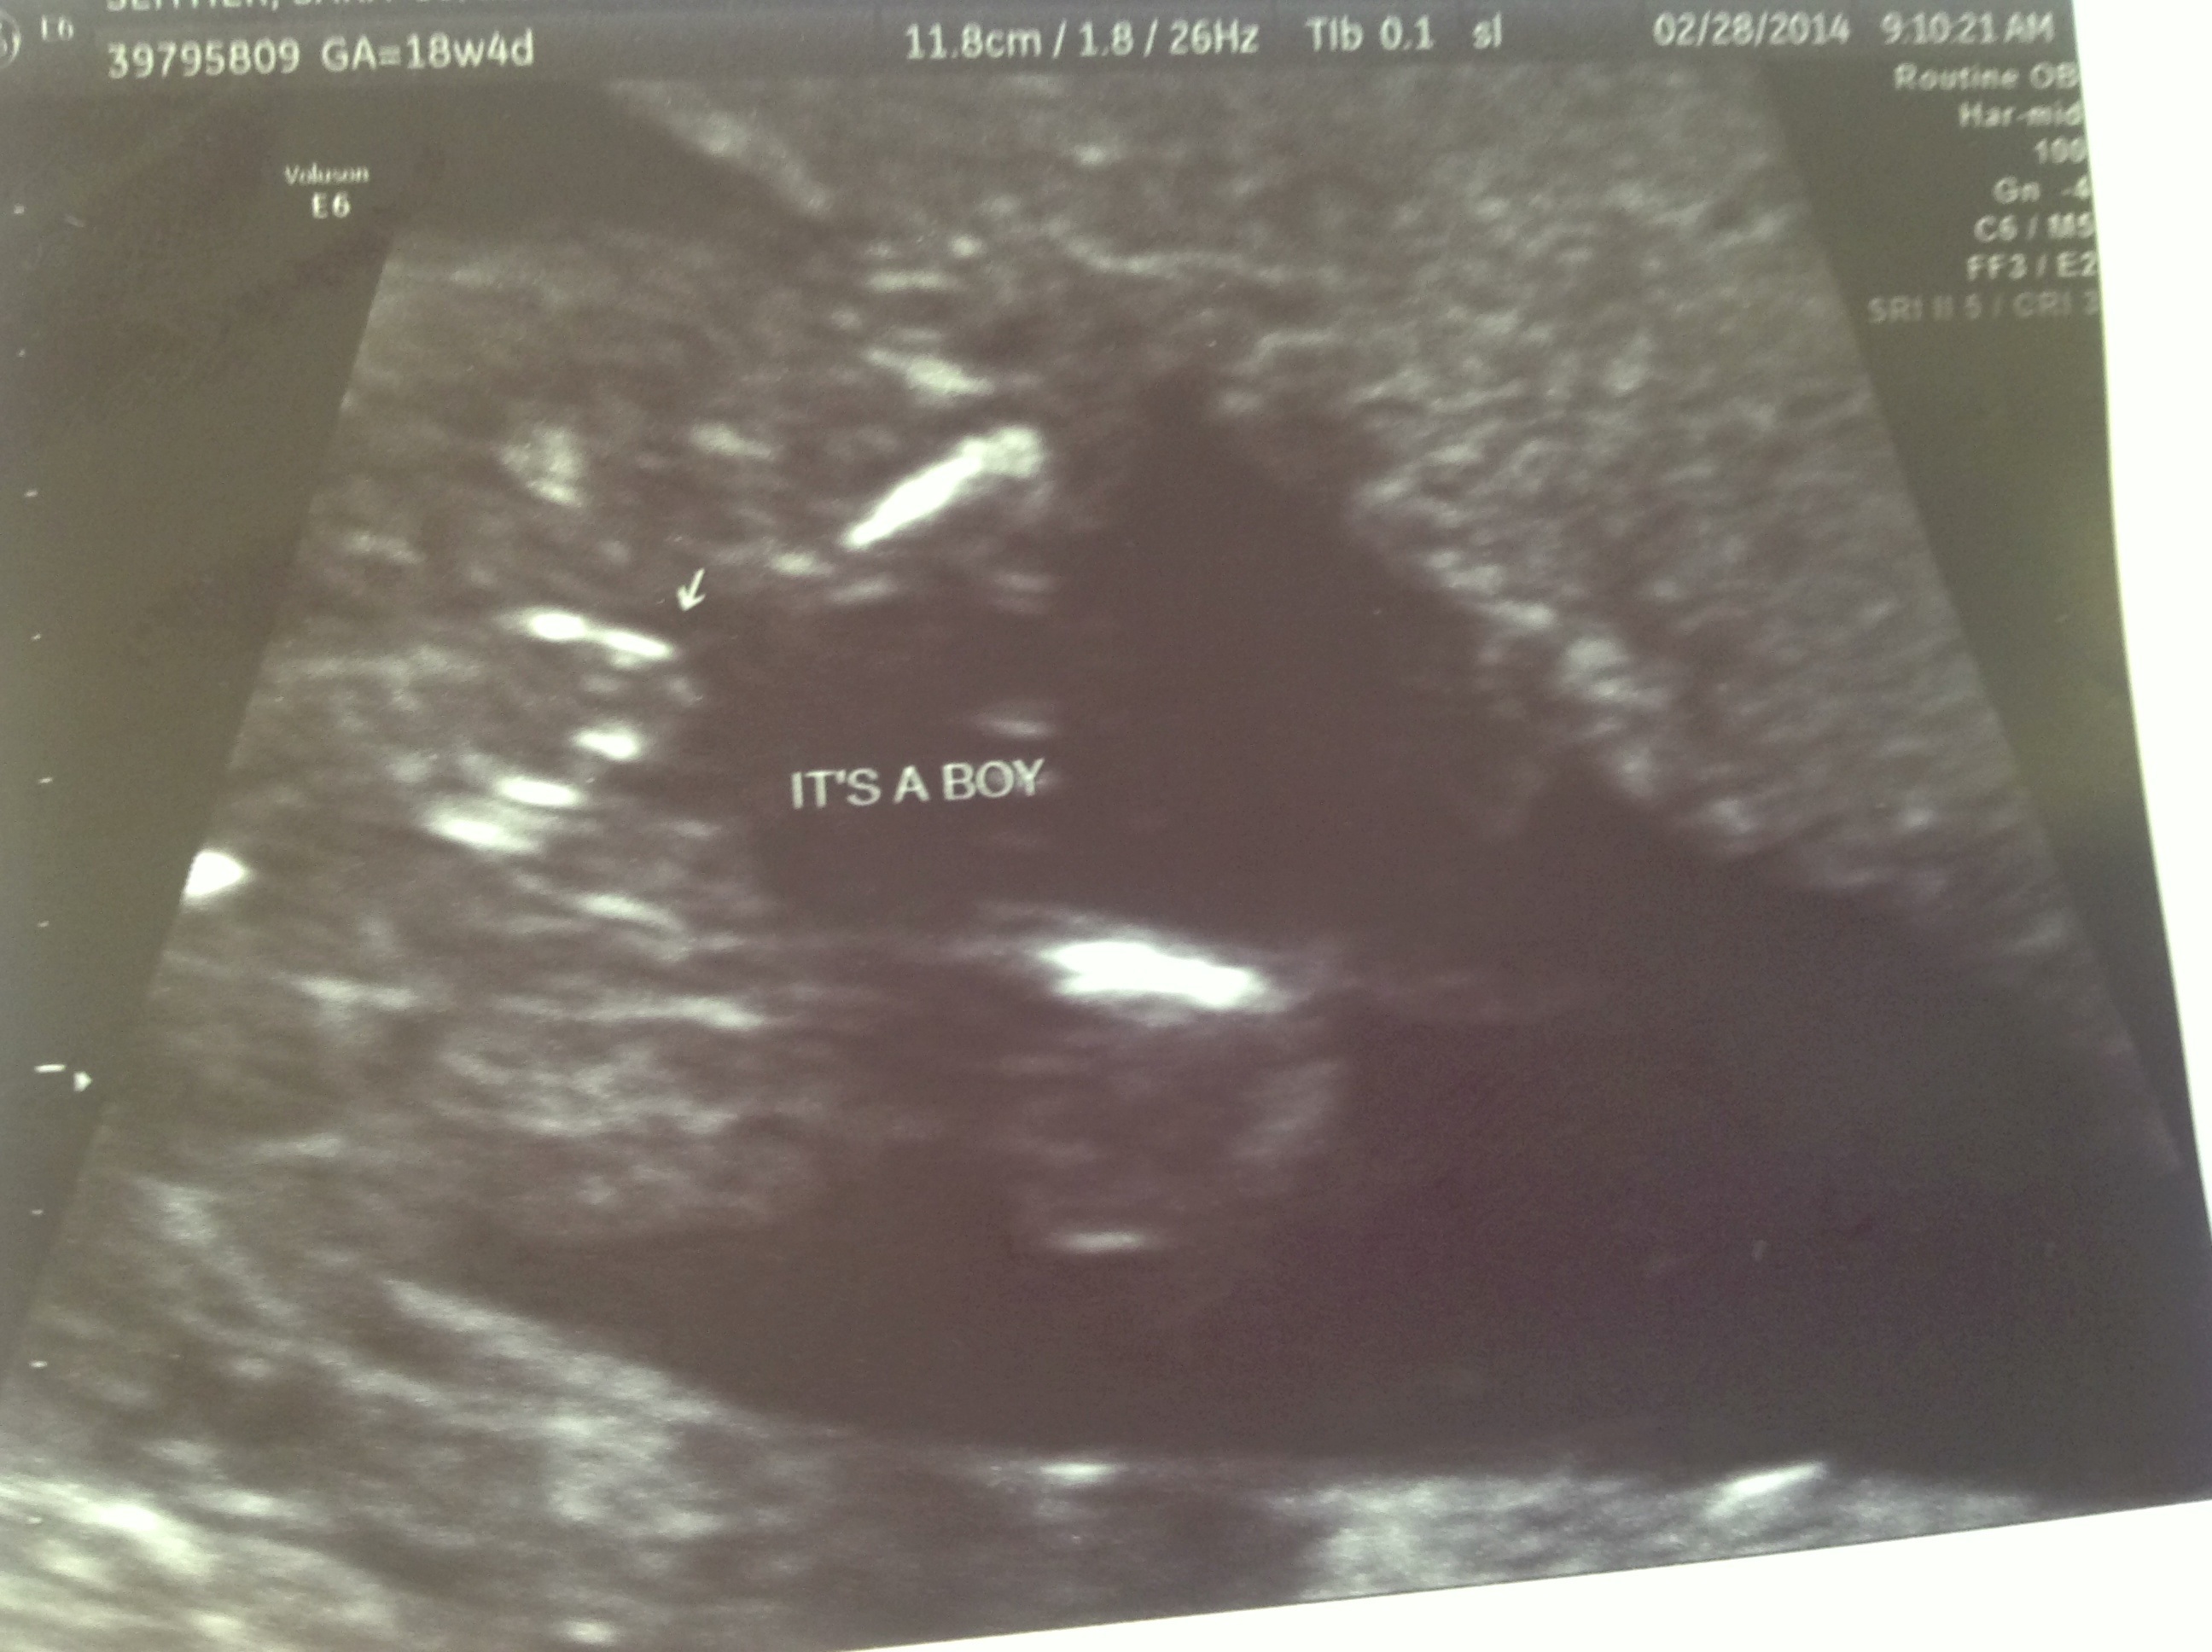

How many weeks? I'd lean boy... There isn't the characteristic 3 lines for girl but I'm not seeing a classic turtle for boy either....

18w4d. I am not seeing either boy or girl!

Definitely boy.

I'm leaning boy, yes. It's very rounded and I think it's not as pronounced because its really zoomed in. I'd want a better shot for 100% confirmation.

Too much between the legs to be girl at that stage. Boy!